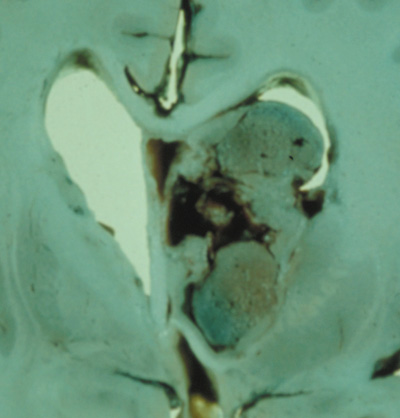

2. Subependymal nodules (SEN) are typically found along the lateral borders of the ventricles and parehncymal brain lesion (“cortical tubers”) (Figs. 14 and 15). Calcification in the first year of life is rare.132

Fig. 14. Tuberous Sclerosis Complex: Sub-Ependymal nodules. These are typically found along the lateral borders of the ventricles.132